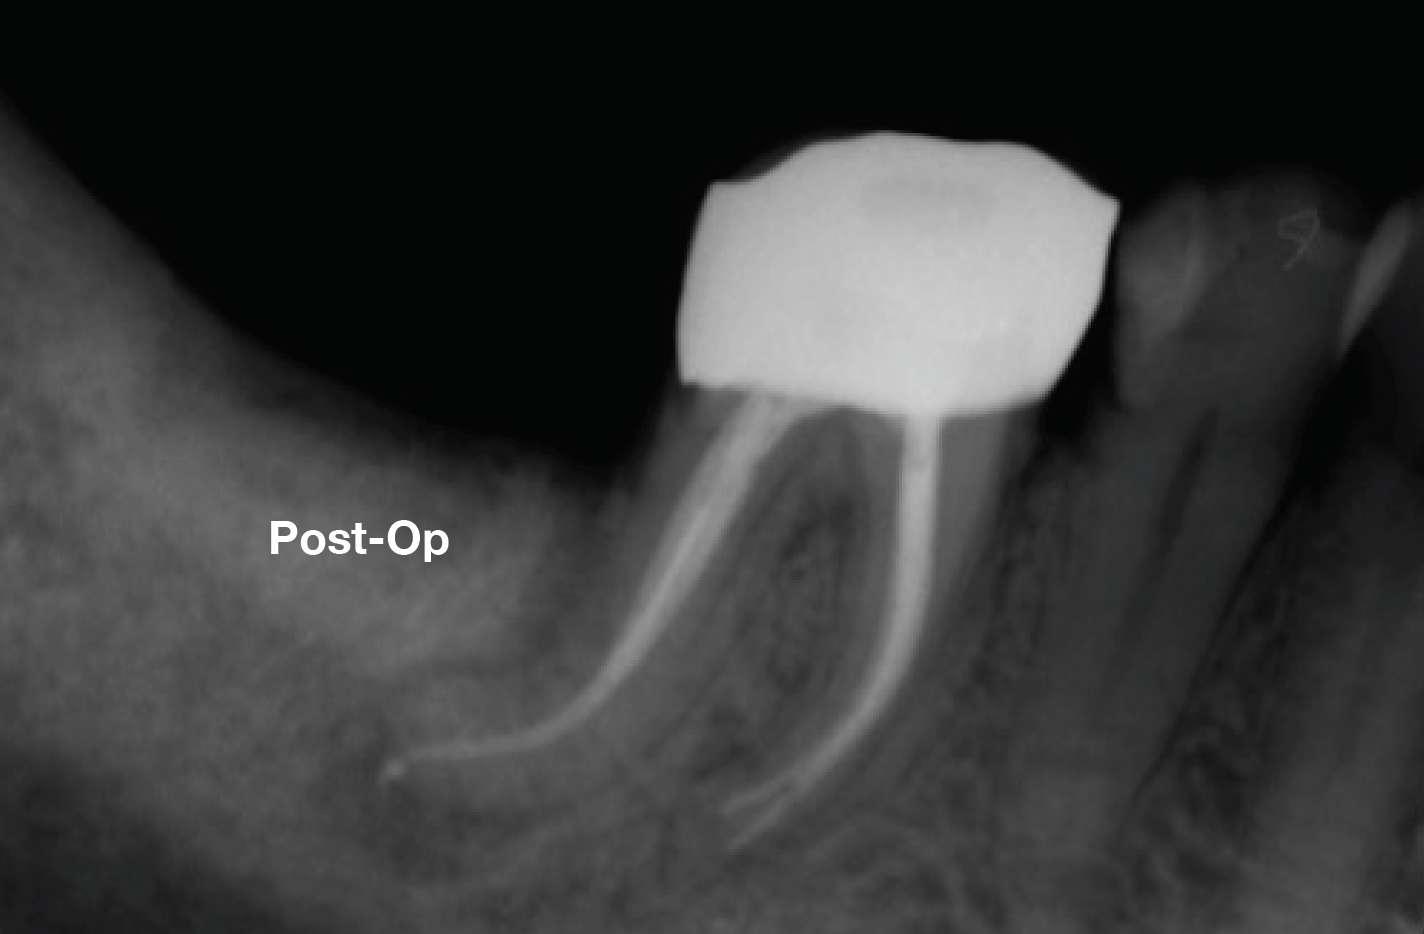

Die Wurzelfüllung erfolgte mit einer einzigen Kegeltechnik unter Verwendung des BUSA EndoSequence Bioceramic Sealer. Das Post-OP-Röntgen zeigt sehr hohe Dichte in der gesamten Länge der Wurzelfüllung.